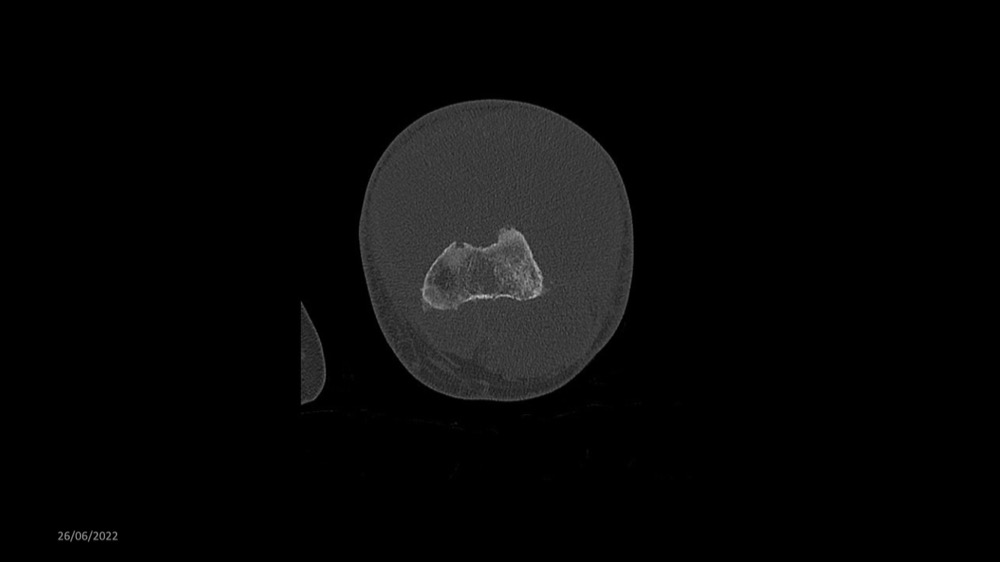

Reichert / Amar / Tordjman / Carlier 29/06/2022